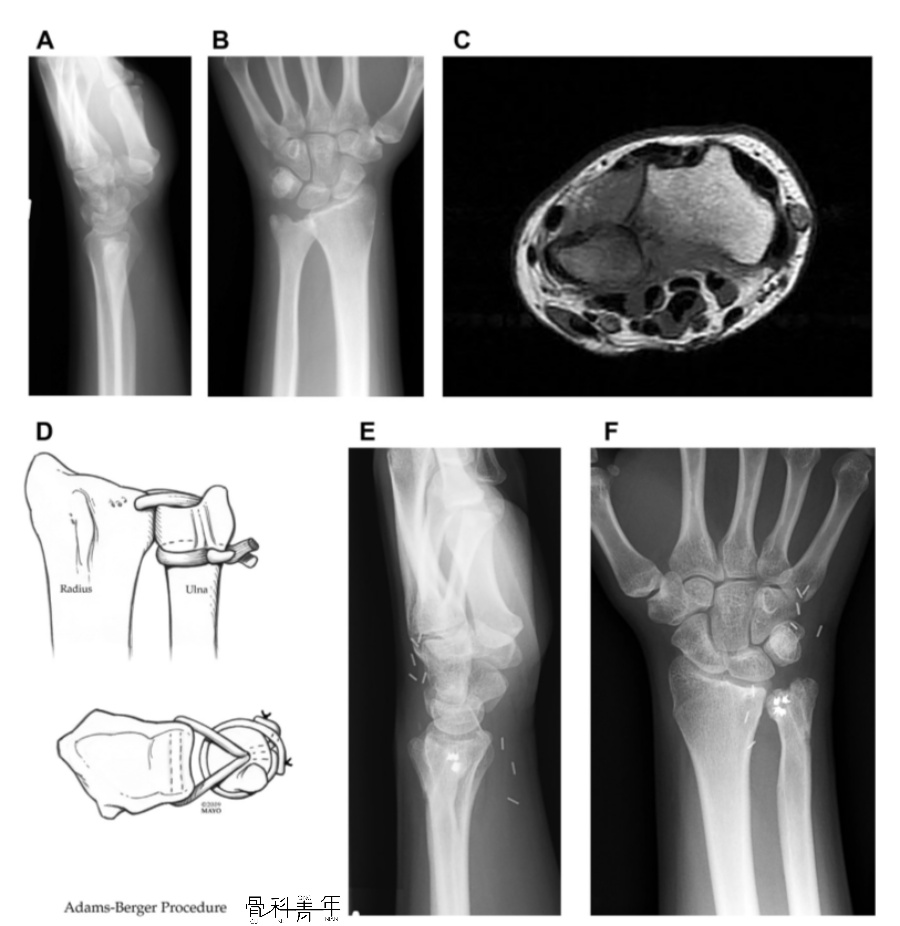

下尺桡关节脱位一例

少见下尺桡关节掌侧脱位二例

总结下尺桡关节脱位的诊治一文梳理